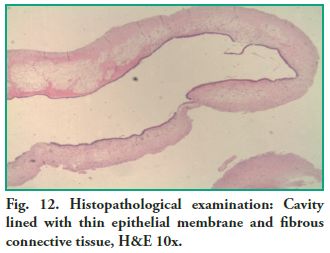

Microscopic description: Cystic cavity lined by a thin membrane made up of pseudostratified ciliated cylindrical epithelium (sinus mucosa), alternating with areas of hyperplasia, supported by fibrous connective tissue, with areas of edema, with plenty of capillaries, some of which are congestive and mixed inflammatory exudates. The content is amorphous and eosinophilic with inflammatory cells (lymphocytes and plasma cells) scattered in mucous material (Figs. 12 and 13).

Microscopic description: Cystic cavity lined by a thin membrane made up of pseudostratified ciliated cylindrical epithelium (sinus mucosa), alternating with areas of hyperplasia, supported by fibrous connective tissue, with areas of edema, with plenty of capillaries, some of which are congestive and mixed inflammatory exudates. The content is amorphous and eosinophilic with inflammatory cells (lymphocytes and plasma cells) scattered in mucous material (Figs. 12 and 13).